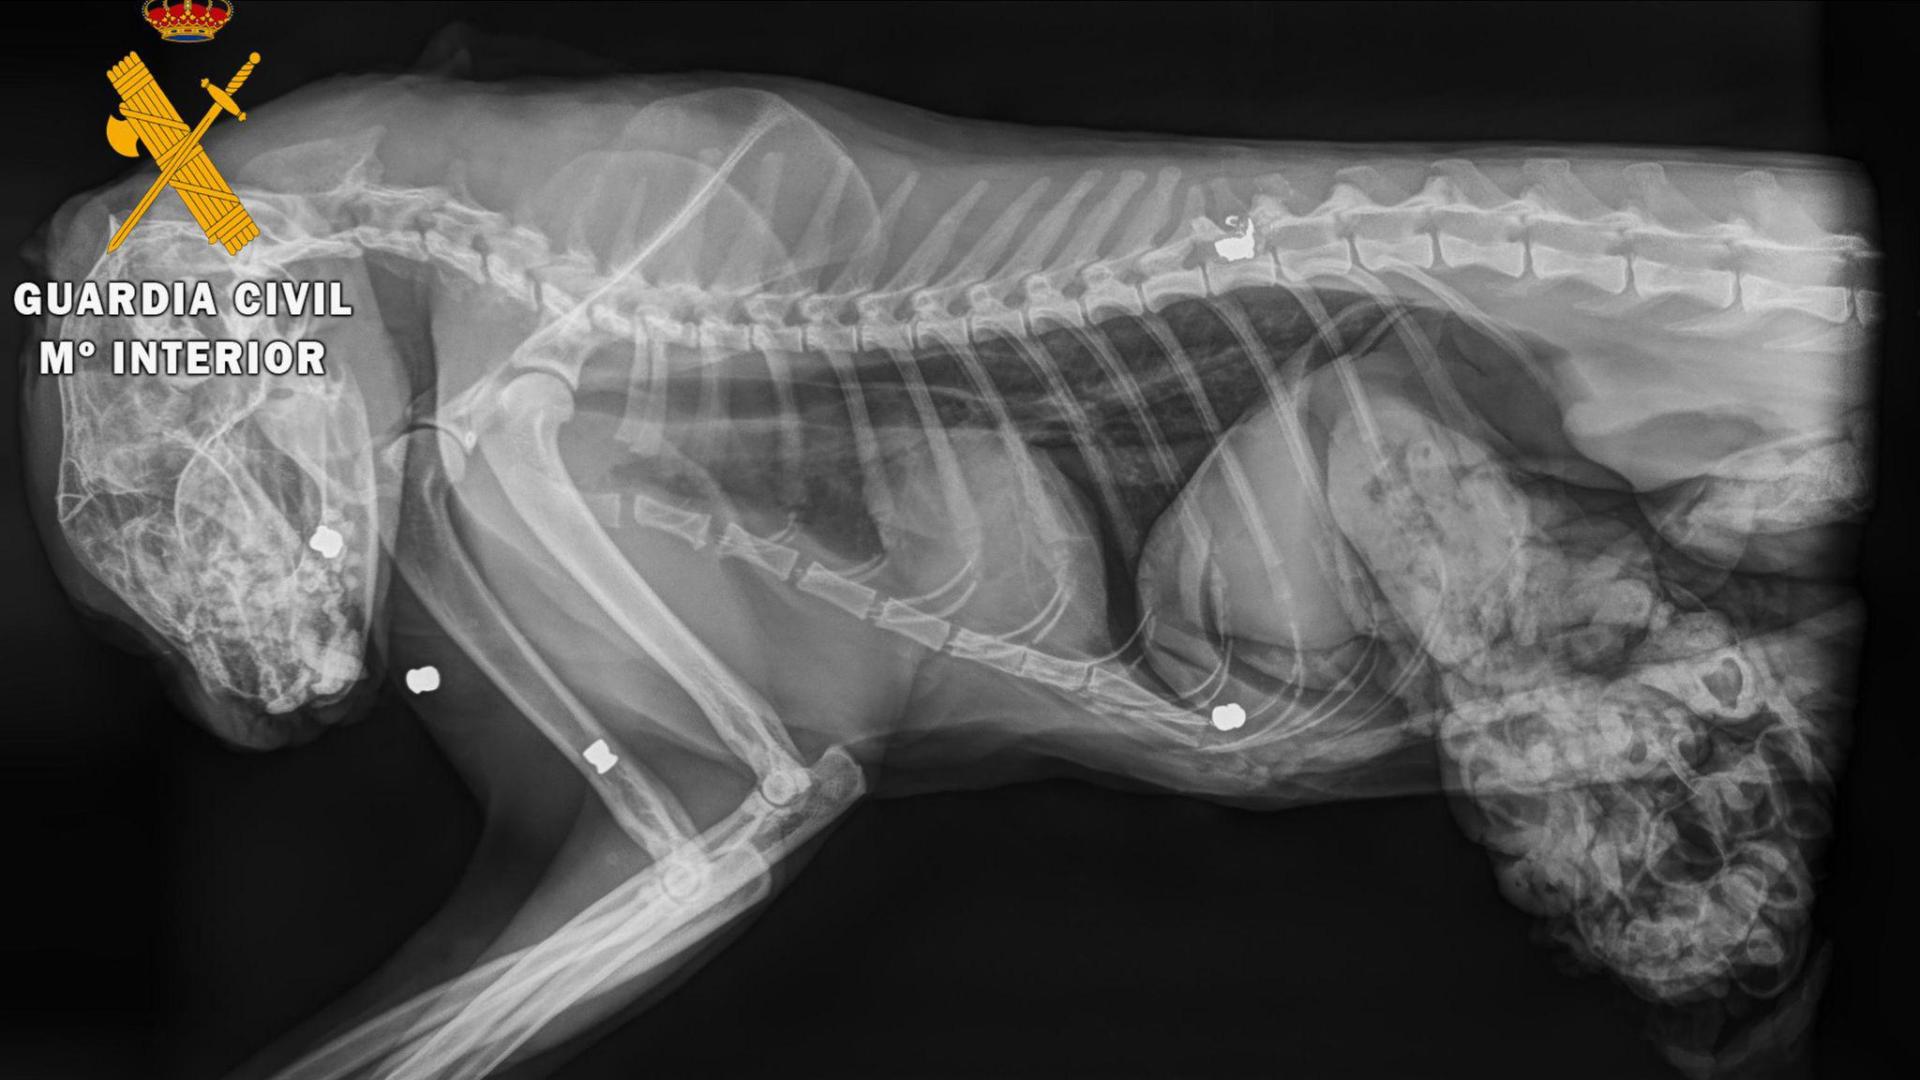

Al cuerpo del gato se le realizó una necropsia en una clínica veterinaria de Estella, donde se determinó que el animal había fallecido por el impacto de cinco perdigones. Se extrajo uno de los cinco proyectiles por si fuese necesario para un análisis.